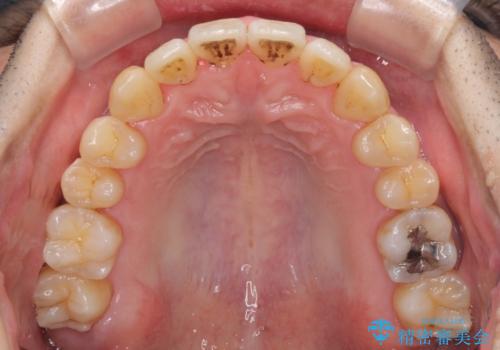

- 上下の前歯の反対咬合を気にして来院された患者様です。

インビザラインを用い、下顎はIPR(歯と歯の間を削る)と歯列全体を後方に移動させ、上顎は前歯を持ち上げることで、反対咬合を改善していくこととしました。

八重歯の歯根が見えている点も気になっているので、矯正歯科治療後に歯肉移植による根面被覆を行うこととしました。

インビザラインによる反対咬合の改善は、上の歯が下の歯を乗り越えていく期間に咬み合わせが非常に不安定となり、治療が長期化することがあります。

また、ワイヤー矯正と異なり歯軸改善の強い力を前歯にかけるため、反対咬合で裏側にある歯の歯肉が退縮しやすくなります。

矯正治療により元々気になっていた八重歯と、反対咬合が改善された歯の2本に対して根面被覆を行い、審美面の改善も達成しました。